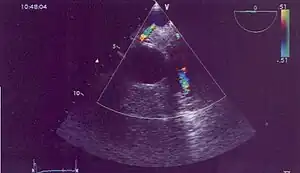

| Possible communication between left coronary artery and pulmonary artery in a 45-year-old woman with Bland-White-Garland syndrome. | |

Historically ALCAPA was diagnosed with conventional angiography. Today echocardiography is easily used. It can provide direct visualisation of the anomalous coronary artery and other associated structural abnormalities, and it can also assess myocardial function .The use of pulse and color-flow doppler can sometimes visualise reversal flow in the pulmonic artery. Other non-invasive methods used are computed tomography (CT) as well as magnetic resonance imaging (MRI) which enable a direct visualisation of the arteries as well as the myocardial viability.[3]